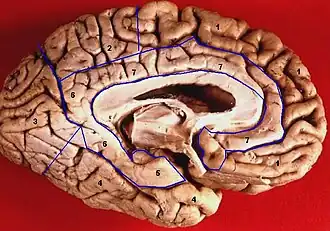

Medial surface of left cerebral hemisphere. Parahippocampal gyrus shown in orange. -  			Human brain inferior-medial view. Parahippocampal gyrus labelled as #5

Coronal section. Parahippocampal gyrus labelled at bottom center. -

Coronal section of hippocampus. Parahippocampal gyrus labelled at bottom. -